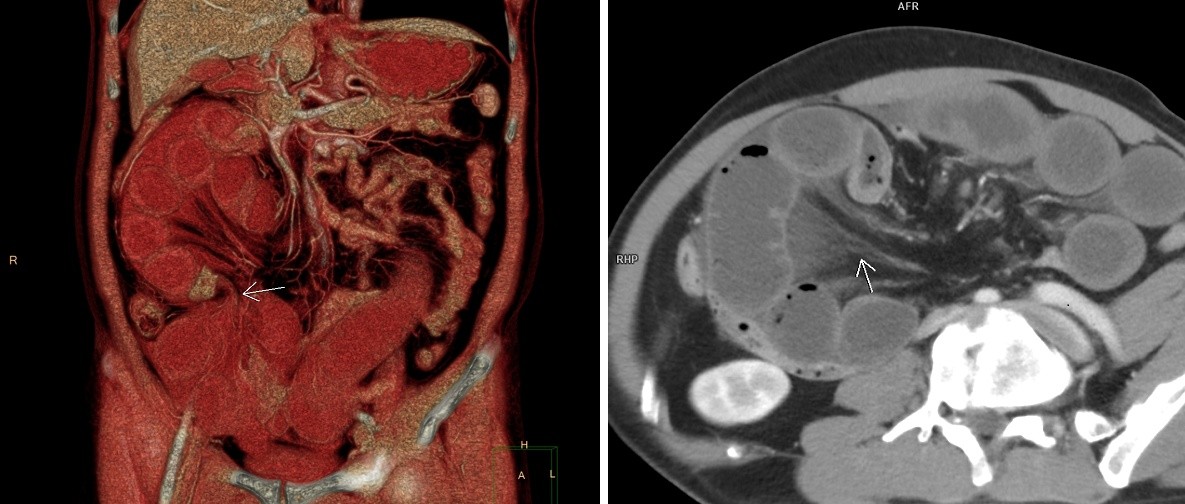

Nhận thấy tình trạng của ông C., các bác sĩ nhanh chóng hồi sức tích cực, chỉ định làm các xét nghiệm cận lâm sàng. Kết quả CT cho thấy tình trạng tắc ruột non cơ học dạng quai kín, nghi ngờ do xoắn ruột. Hình ảnh cản quang cũng cho thấy một đoạn quai ruột non bắt quang kém hơn các quai ruột còn lại, nghi ngờ có hoại tử. Chỉ số bạch cầu tăng cao (13.3 x 10⁹/L), hemoglobin giảm (còn 98 g/L), cho thấy nguy cơ nhiễm trùng và tổn thương mô vô cùng nghiêm trọng.

Kết quả CT cho thấy tình trạng tắc ruột non cơ học dạng quai kín, nghi ngờ do xoắn ruột